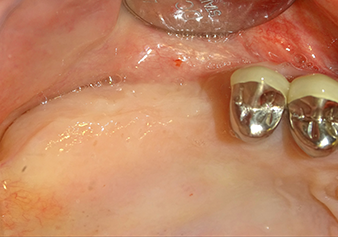

Preoperative findings: The alveolar ridge has healed well, including sufficiently broad, keratinised gingiva

Fig.1: Preoperative findings: The alveolar ridge has healed well, including sufficiently broad, keratinised gingiva.

A 49-year-old female patient, a non-smoker and with nothing remarkable in her general medical history, was referred to our oral surgery practice for surgical extraction of tooth 16 and subsequent implantation. After the extraction, the patient experienced mild sinusitis trouble with the resultthat we initially waited six months before carrying out the measure. The residual bone height at the planned implant position measured 3-4 mm (Fig. 1 and 2).